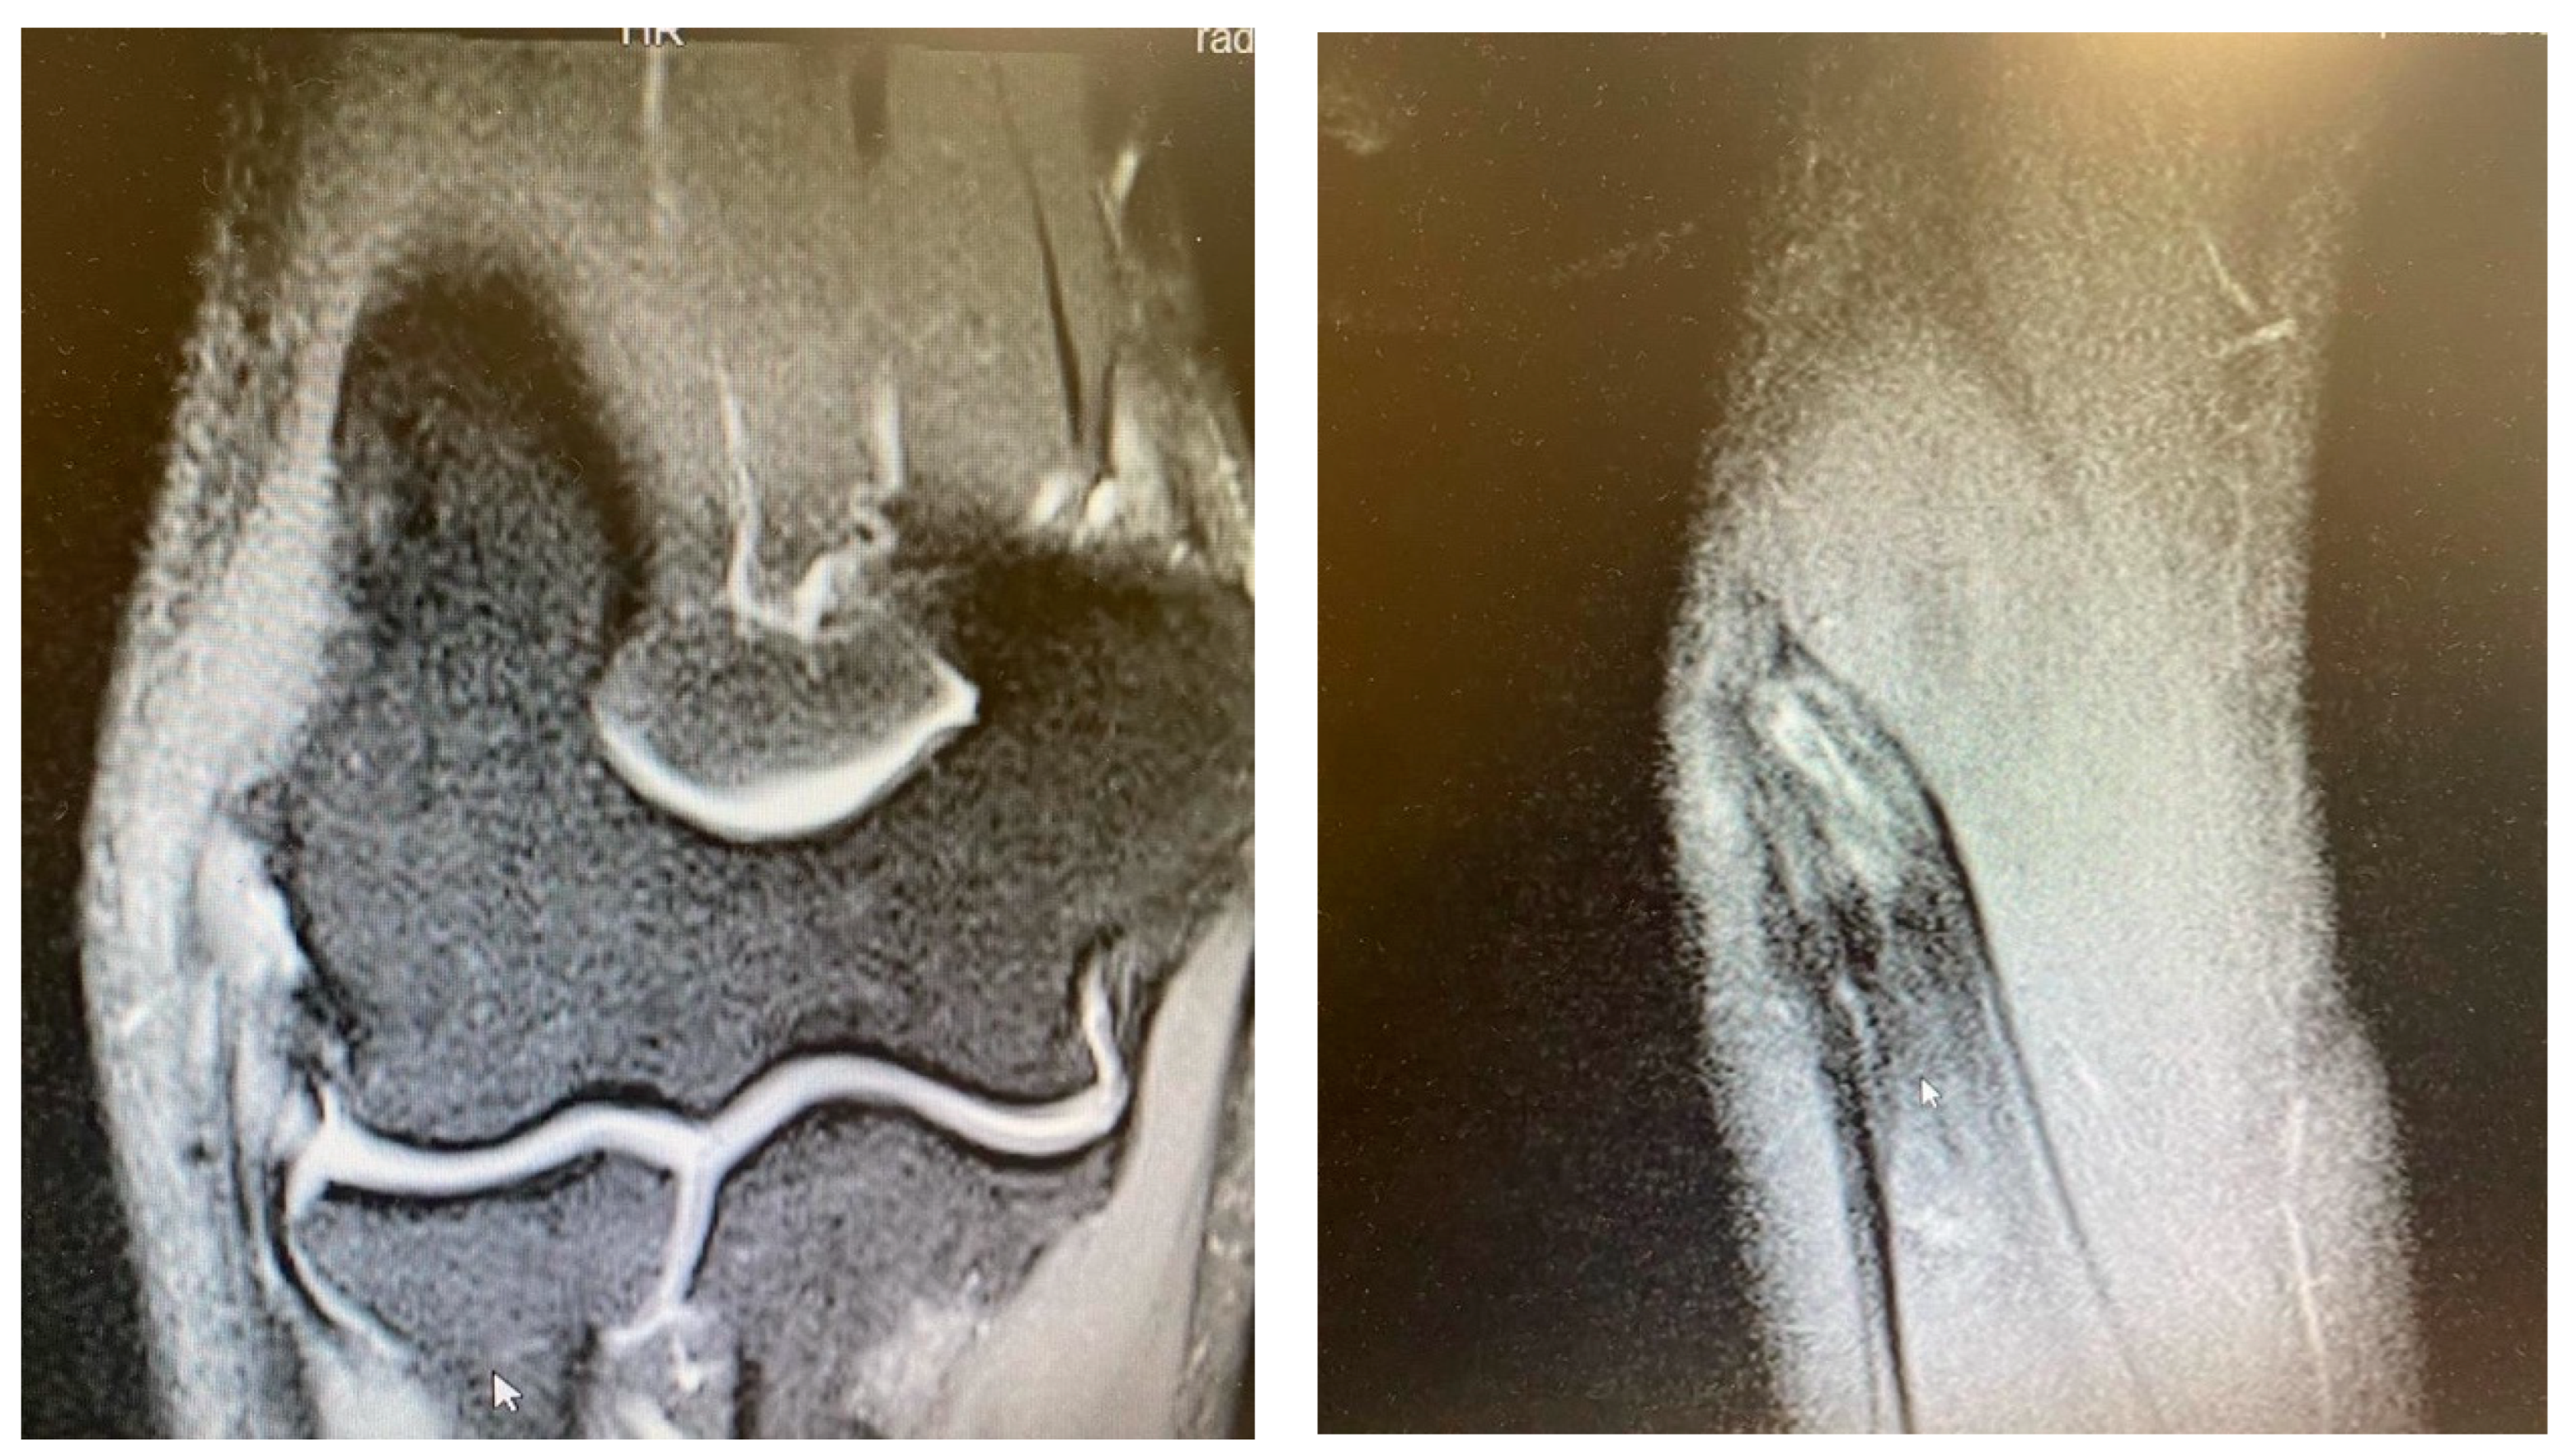

- It is contingent on the integrity of the CEO, whether it is intact, has a moderate or extensive partial tear, or is completely ruptured with or without retraction. This evaluation can be conveniently conducted via MRI.